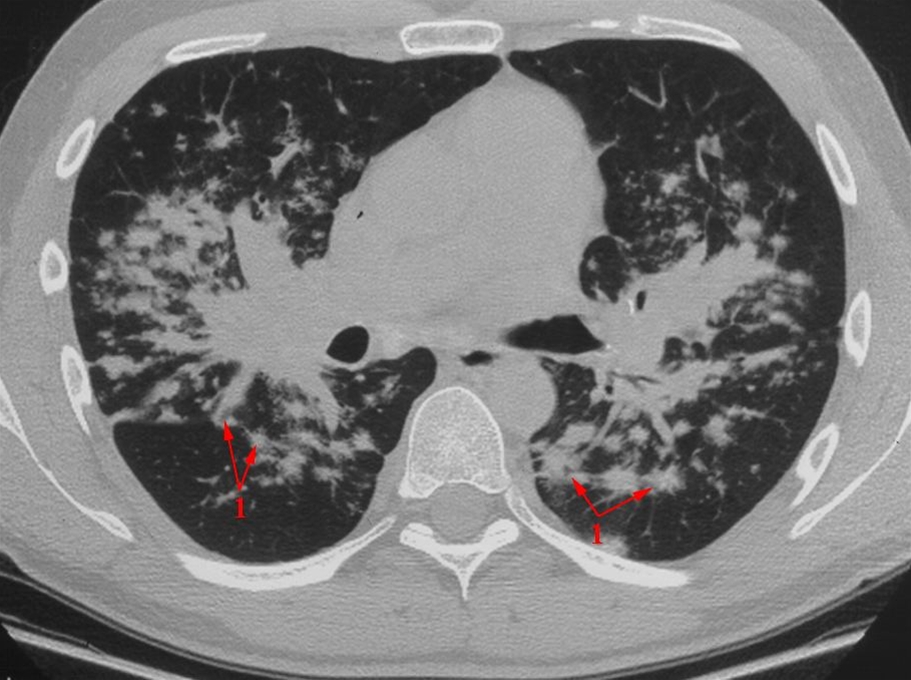

HRCT (High resolution CT). Et millimeter tykt CT-snit. Uregelmæssige små knuder (granulomer) med hovedsagelig central fordeling